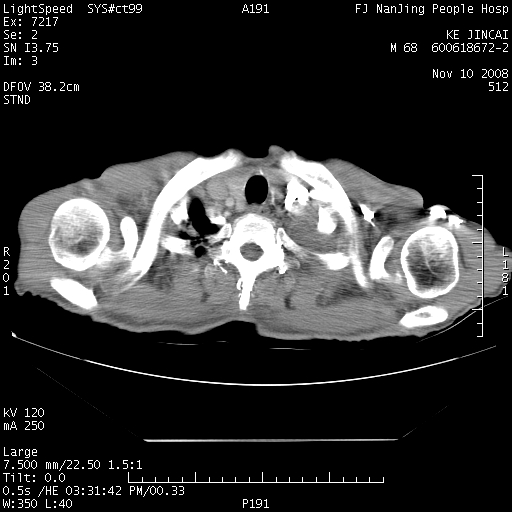

是个很有看头的病例,咋人气那么不旺?没多少人兴趣呢?这个病例几大怪:1   恶性肿瘤侵犯心肌左房怪,心肌一般不会被恶性肿瘤侵犯吧?2   左下肺均匀实变怪,内无含气,有别一般不张实变,含气肺泡完全为液体取代,而非一般不张实变的肺萎陷,冷不丁还以为是肿大的脾脏3   肿瘤本身怪,像tb肺不张4   这么有看头的病例没人气怪。呵呵。

追查病史,咳嗽,患者无发热,血象不高。据说2年前胸片检查怀疑肺ca曾行纤支镜检查,病理未见到癌细胞。无确切资料。